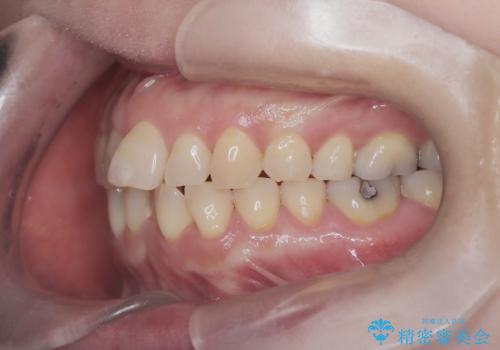

今回の矯正治療では、歯の色に近い目立たない審美ブラケットとワイヤーを使用しました。

スペース確保のために、まず奥歯全体をわずかに後方へ動かす遠心移動を実施し、前歯を並べるためのスペースを確保。さらに、安全性に配慮しながら歯の側面をわずかに削るIPRを併用し、デコボコを解消しました。

ワイヤー矯正ならではの確実な歯のコントロールにより、当初の計画通り約1年という短い期間で、前歯のガタつきが解消。見た目が美しく整っただけでなく、清掃しやすい機能的な歯並びを獲得していただけました。